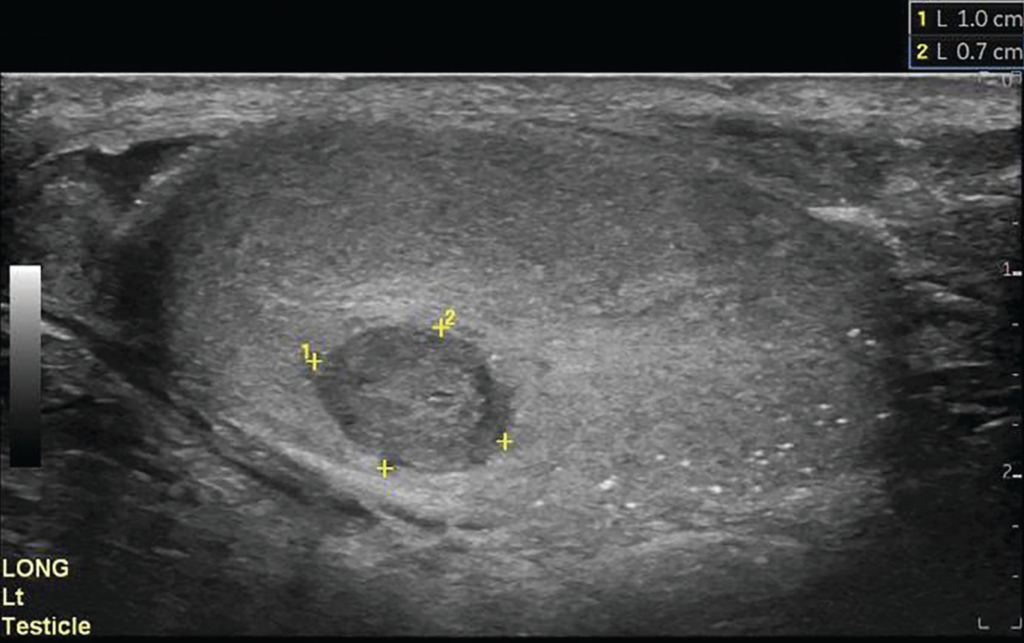

Seminoma – hypoechoic lesion outlined by yellow markers. Source: Hwang & Alexander, 2023.

- Findings: Seminomas usually appear as homogeneous, hypoechoic masses with smooth borders. Non-seminomatous tumors are heterogeneous with ill-defined margins, cystic areas, or calcifications.

- Sensitivity: Seminoma: 76.8%; Nonseminoma: 57.7%

- Specificity: Seminoma: 84.6%; Nonseminoma: 96.4%